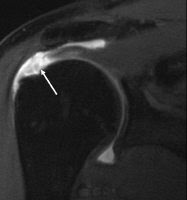

Rotator cuff repair surgery and postoperative rehabilitation continue to be some of the most debated topics on the shoulder at orthopedic and physical therapy conferences.  Numerous studies have been published showing the failure rate of rotator cuff repair surgery ranges anywhere from 25-90%.

rotator cuff tearWhile this failure rate is certainly alarming, the term “failure” must be defined.  In traditional study models, success is defined as an intact rotator cuff, which makes sense.  However, one of the more interesting findings in most of these studies is that despite the “failed” repair, most patients are quite satisfied with their functional status and outcome.  This really does have to make you question how we define “failure” as patient outcomes and satisfaction seems more important than radiological findings.

A recent study in the Journal of Shoulder and Elbow Surgery looked at this exact question.  The MOON Shoulder Group, which is a multi-center network of research teams around the country, followed a group of 381 patients with atraumatic full-thickness tears of the rotator cuff for a minimum of two tears.  The mean age of the patients was 62 years with a range of 31-90 years.

At the six-week mark, patients were assessed and 9% chose to have rotator cuff repair surgery.  Patients were again assessed and the 12-week mark.  At 12-weeks, an additional 6% chose to have surgery.  In total, 26% of patients decided to have surgery by the 2-year follow-up mark.  Statistical analysis revealed that if a patient does not choose to have surgery within the first 12-weeks of nonoperative rehabilitation, they are unlikely to need to surgery.

Nearly 75% of patients avoided rotator cuff repair surgery by performing physical therapy despite having full thickness cuff tears. [Click to Tweet]